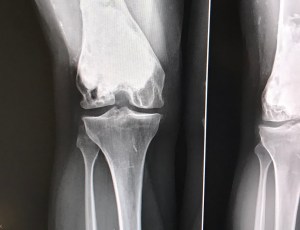

She gave me a cortisone shot for the pain. She said that I have acute arthritis that is shocking for someone so young. She said that the mass that has developed in my distal femur is something we must investigate further but she is really convinced that it isn’t the Giant Cell Tumor coming back. She said that they usually only come back within the first 5 years of diagnosis, not 17!

I have to get an MRI, collect my records from the hospital in Halifax and have a chest x-ray done. Nothing was said about having a bone biopsy – I was really apprehensive about that.